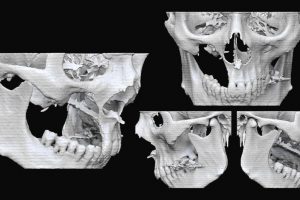

Après avoir affirmé pendant des années que les effets bénéfiques de l’utilisation de la radiothérapie sur les cancers de la sphère ORL n’étaient pas assez importants pour justifier de tels […]

15 juin 2016 - Dans les médias, Recherche